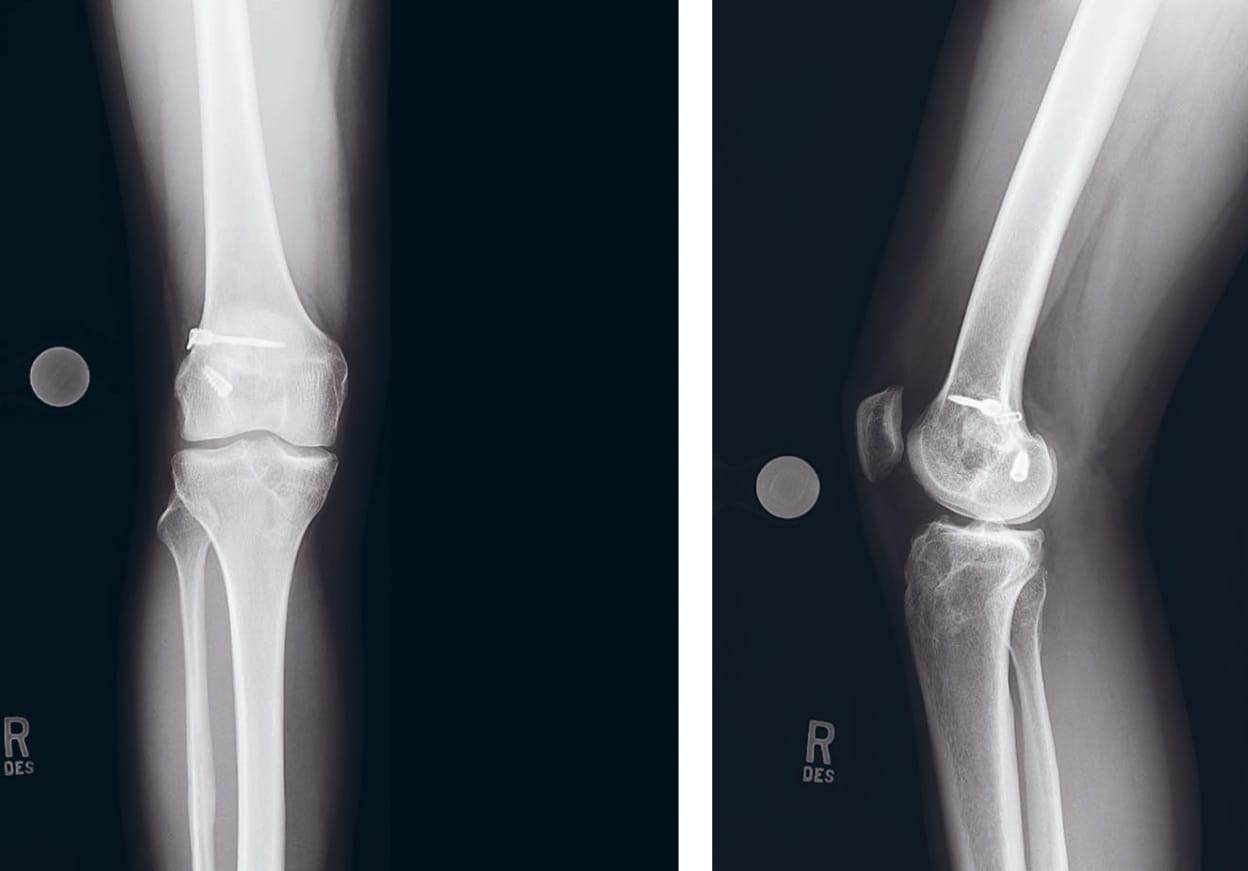

This case report details the procedure of a 28-year old female physician assistant in family medicine who presented to our clinic complaining of right knee instability after four prior operations (three ACL reconstructions and one bone grafting) by other surgeons. The patient first tore her ACL in high school, and had a subsequent hamstring autograft reconstruction. She then had two further re-injuries, for which she underwent revision on both occasions with allograft. The second revision was a two-stage procedure done with bone grafting. Her last ACLR was performed 6 years ago after her knee gave way on a trampoline.

A two-stage reconstruction was indicated, given the patient’s severe tibial tunnel expansion to 23mm. For the ACL, a contralateral patellar tendon autograft was recommended. For the first stage of the two-stage reconstruction, bone grafting with allograft as well as hardware removal for the metal femoral screw was recommended. The second stage would be a contralateral patellar tendon autograft reconstruction with lateral extra-articular iliotibial (ITB) band tenodesis.